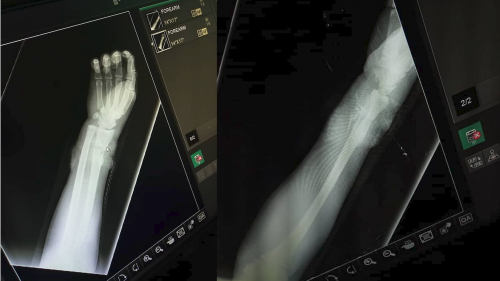

The bullet reportedly damaged Sadiq’s radius and ulna bones as well as the tendons on his wrist.

See Photos: